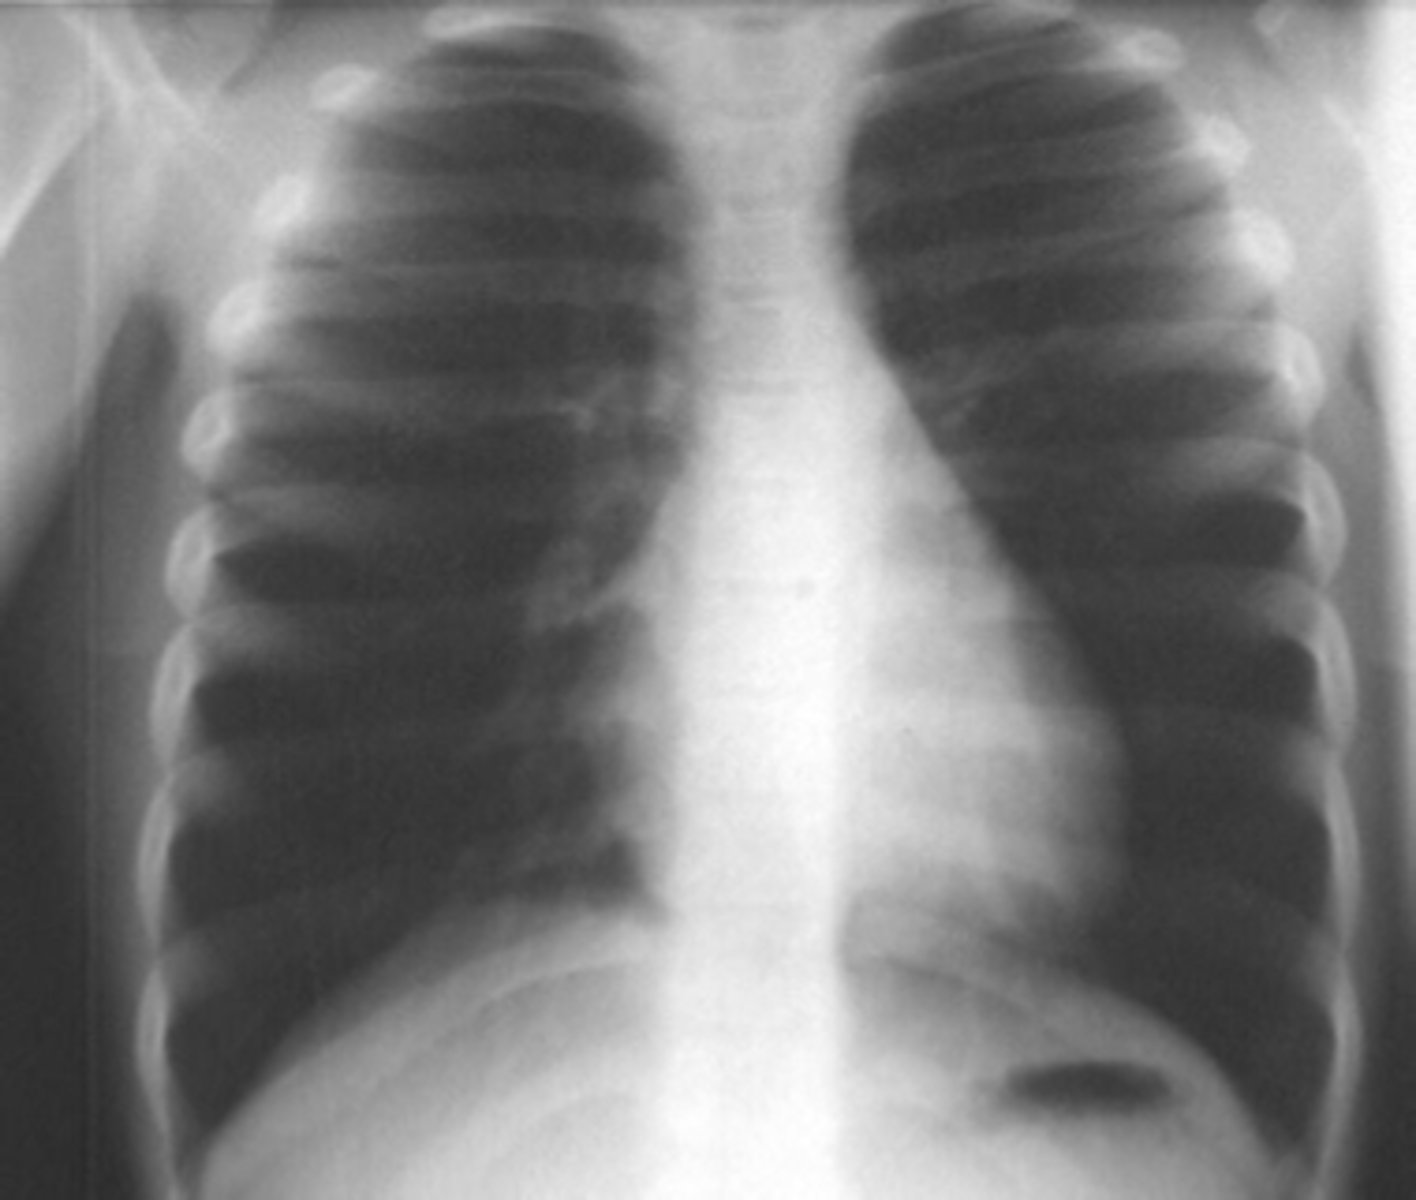

RUL bullae

knowt flashcard image

Flattening of hemidiaphragms

& blunting of costophrenic angles, Increased AP diameter (barrel chest), bullae or large air cavities indicates

hyperinflation

COPD/Emphysema